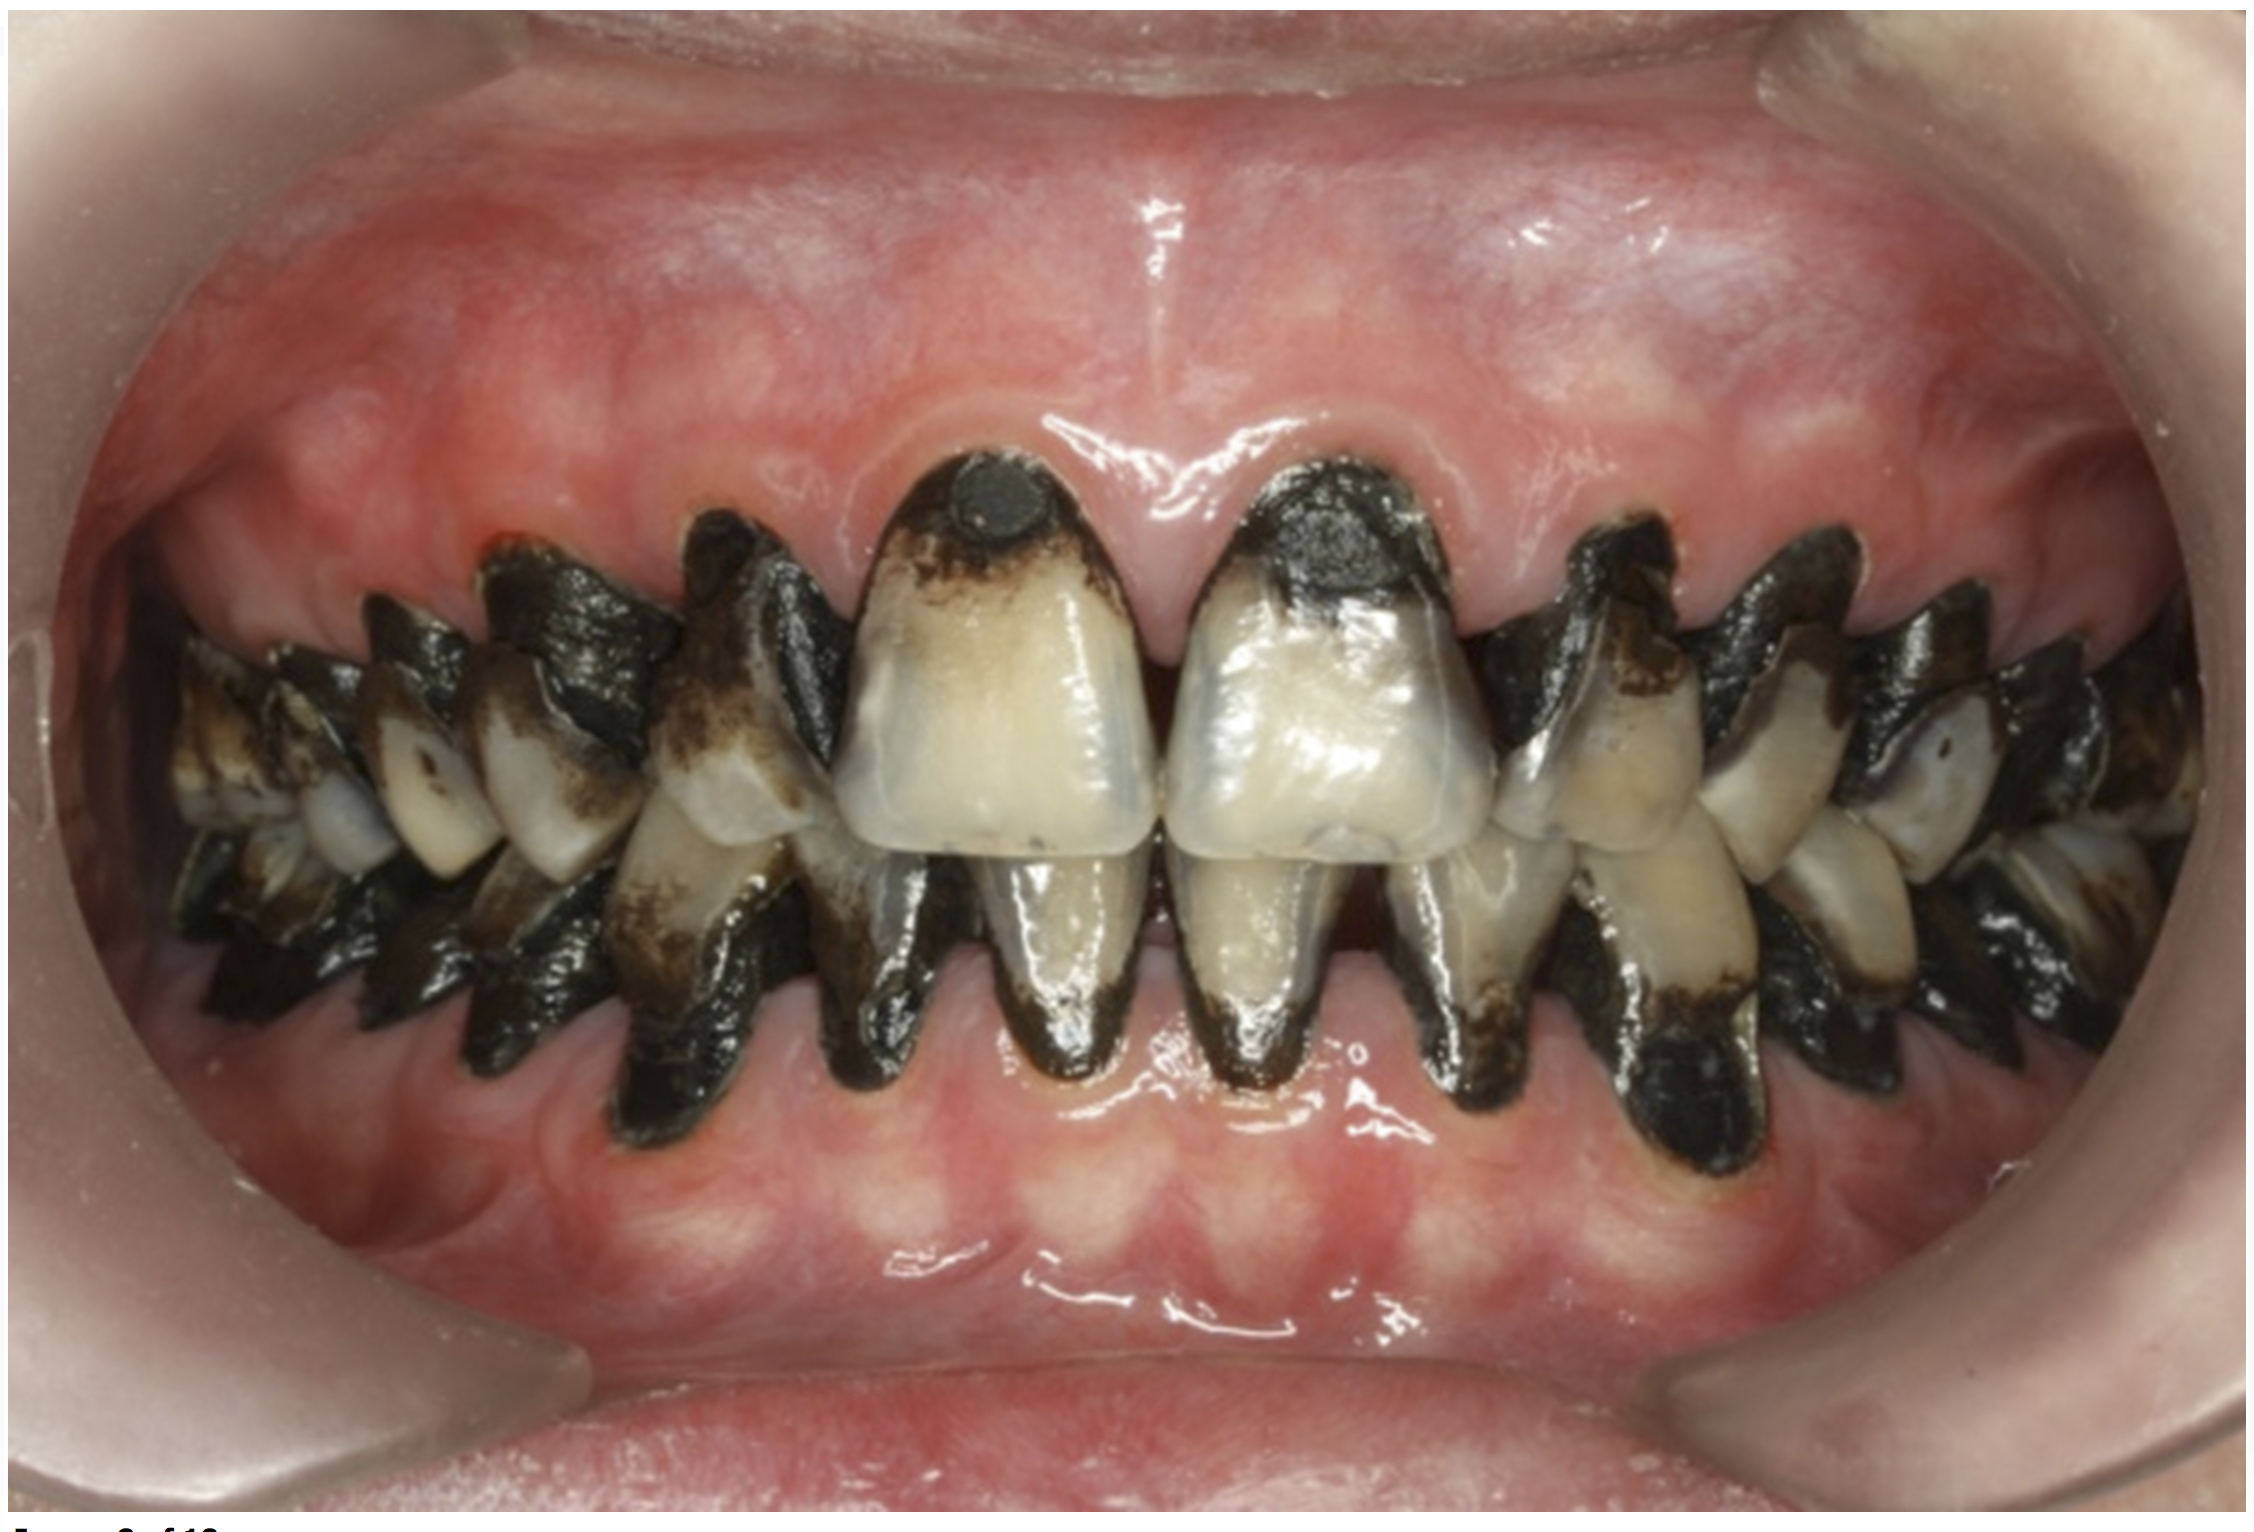

The inherent disadvantage of SDF is that the caries lesions will be stained black after SDF application. SDF stops caries progression by forming a hard, blackened, impermeable layer on the tooth surface that is resistant to caries (Figure 5 through Figure 9). The authors’ clinical observations are that the darker the color, the more likely the caries arrested. Some patients may not be pleased with the esthetics of this treatment outcome; therefore, it is important to inform the patients and parents (for child patients) about this treatment outcome. Moreover, SDF can stain clothes and the skin of the body. Though it does not cause any pain or damage, an SDF stain on skin cannot be easily washed away. It takes around 7 days for it to disappear, and the stain on clothes is permanent.22

There is no consensus on the frequency of application, and 38% SDF has been used annually or biannually on clinical trials in children23,31,33,34 and in elderly.30,35 Yee and his co-worker found one-off application of 12% SDF was ineffective in arresting caries in children.31 The present authors applied 38% SDF weekly for 3 weeks to speed up the process of caries arrest and for treatment of rampant caries.36 One of the present authors’ case reports demonstrated that three weekly applications of 38% SDF can arrest rampant caries and relieve pain from hypersensitivity on a teenager. The SDF-treated caries were found arrested, and they turned coal black in appearance (Figure 9).

Fig 5. Use of 38% SDF to arrest coronal caries in primary teeth of a young child. The arrested carious lesion had a hard, blackened, and impermeable layer.

Figure 5

Fig 8. Use of 38% SDF to arrest rampant caries in a young teenager: pre-treatment intraoral frontal view of rampant caries. (image from Chu, et al, 2014, ref 36 [reprinted with approval])

Figure 8

Fig 9. Use of 38% SDF to arrest rampant caries in a young teenager: frontal view of arrested caries after consecutive application of SDF for 3

weeks. (image from Chu, et al, 2014, ref 36 [reprinted with approval])